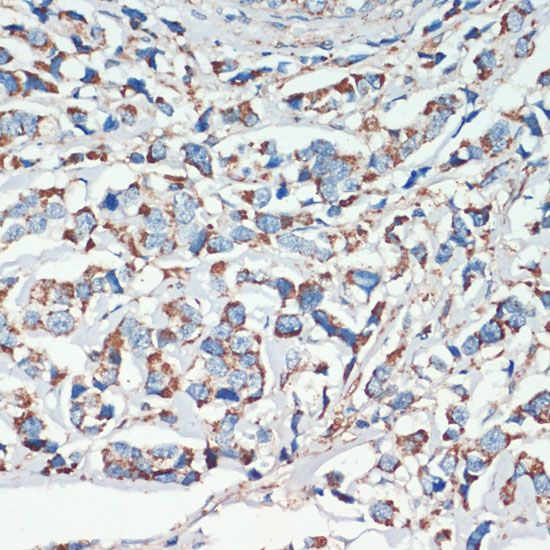

Immunohistochemistry of paraffin-embedded human lung using APC antibody.

Immunohistochemistry of paraffin-embedded human colon using APC antibody.

Immunohistochemistry of paraffin-embedded human breast cancer using APC antibody.